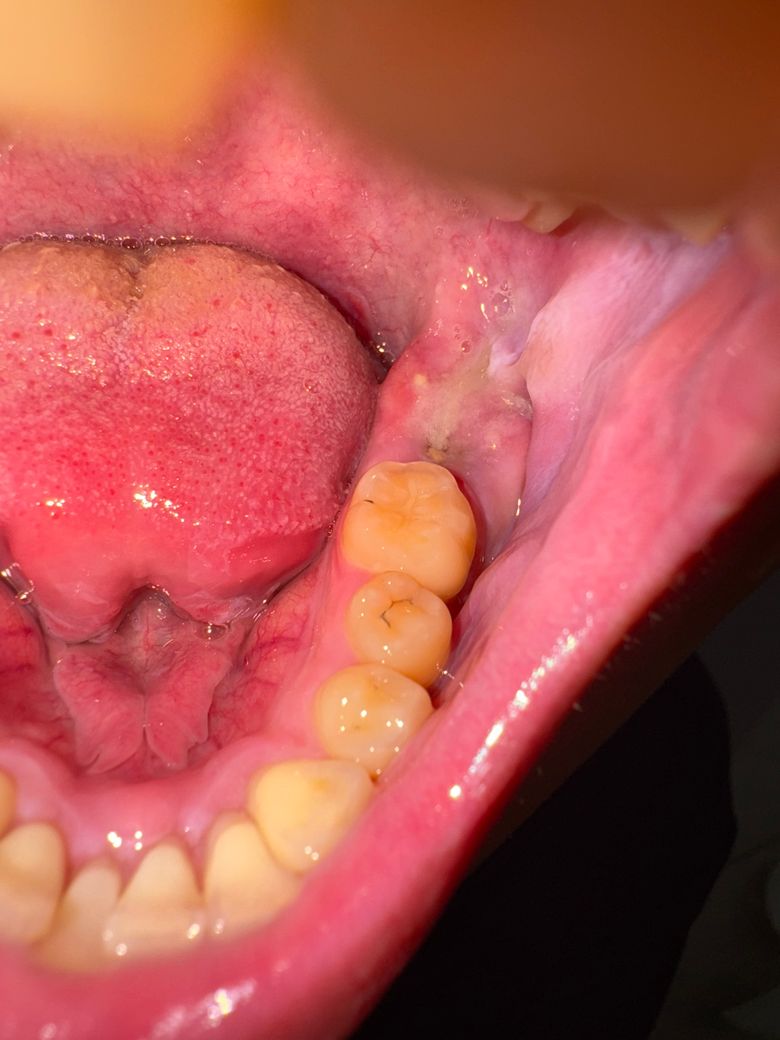

발치 후 치조골 노출과 관련된 질문입니다

전체적으로 충치가 많아 어금니 4개 발치 후 사랑니를 어금니로 사용하는 치료 진행중입니다. (과잉진료.. 는 아닙니다.. 이미 제 눈에도 다썪어 없어진 치아였습니다.) 5/13 발치하였고 5/20 뻐근해서 병원에 이야기 하였으나 옆에 사랑니가 자라나고 있어서 염증 소견 있어 진통제와 항생제 처방 받아 6일째 먹고 있습니다. 드라이소켓은 아니라고 하셨습니다. 오늘 양치 중 확인해보니 어금니 부분에 피브린막도 없고 안에 약간 주황빛 ? 에 흰색 무언가가 보입니다. 치조골 노출인 것 같기도 하고 잘 모르겠습니다. 엄청 욱신거리지는 않으며 5/20 병원 갔을 때랑 마찬가지로 조금 뻐근 하고 욱신거리긴 합니다.

그 이전 사진입니다 (5/25)

그 이전 사진입니다 (5/23)

세장 비교해봤을 때, 피브린 막이 떨어진 것도 같고 점점 사랑니 부분이 나오고 있는 것도 같습니다.

어떤 상황인지 궁금하고 어떤 조치를 받아야하는지.. 궁금합니다.

• 1번 째 사진

• 2번 째 사진

• 3번 째 사진

사진상에 보이는부분을 치과에 가셔서 체크를 해보시는게 좋을것같습니다. 부골이라면 마취후에 제거를 하셔야될것같습니다.

사진으로 봤을 경우에는 해당 부위에 혈병 등이 형성된 것으로 보입니다. 해당 부위를 자극하지 않는 것이 좋으며 사랑니를 발치한 부분은 보통 2주 정도 지나면 아물게 됩니다.

1. 잇몸 치유 과정에서 생기는 다양한 염증, 육아조직으로 보입니다

2. 그 뒤 매복된 사랑니는 사실상 손상없이 꺼내기가 어려운데요 사랑니로 발치한 두번째 큰 어금니를 대체하기로한 치료계획에 대해 다시 설명 들어보세요